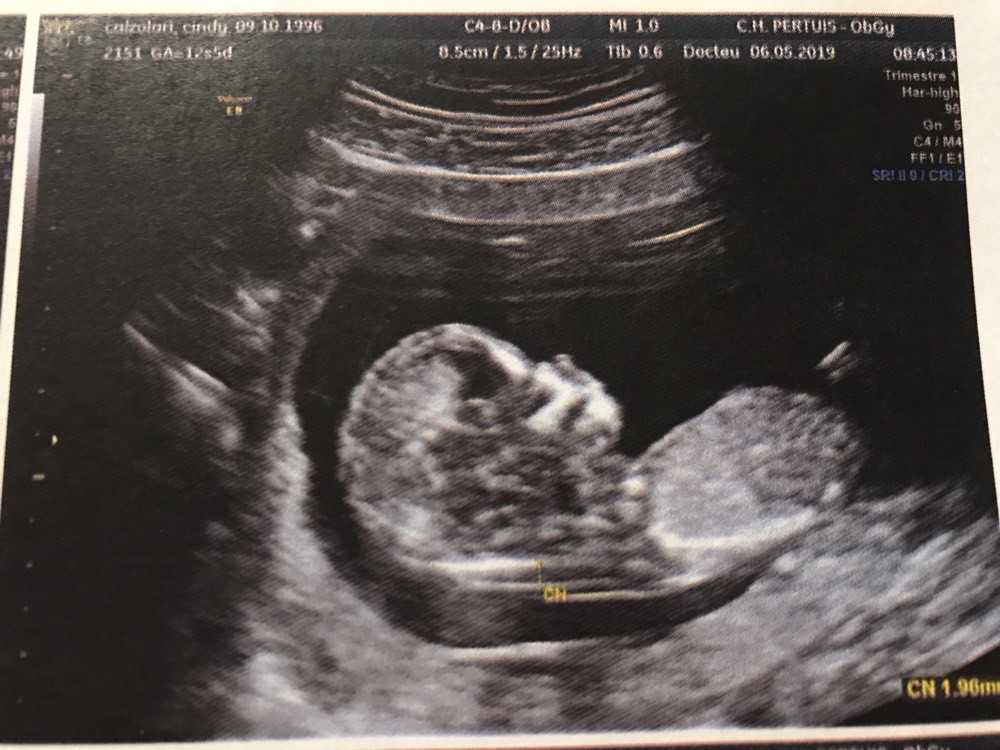

at 856 am ET on 247WallStcom This Top Beer Maker Is Going to Produce Cannabis Beverages This Year at 812 am ET on Motley FoolL'aspect est celui d'une fille quand les deux droites ne se rencontrent pas Le taux d'erreur est de 0,9% 3 % Dans toutes les séries il y a plus d'erreurs quand on annonce une fille L'aspect est celui d'un garçon quand l'angle ainsi tracé est supérieur à 30° Le taux d'erreur est de 0,2%J'ai eu mon écho des 13 SA et gygy m'a fait un pronostic de sexe en voyant le tubercule génital de dessous (bébé est de dos) je pensais qu'on pouvait mieux voir de profil

Selon la « nub theory » ou méthode du bourgeon génital, on peut, dès 12 semaines d'aménorrhée environ, avoir une idée du sexe de bébé en étudiant l'angle entre le bourgeon et la colonne vertébrale Voilà l echographie du 1er trimestre est passée et j aimerai connaitre le sexe de mon bébé A ~ 39 SA ~ 2kg960 50 cm ~ accouchement nature,Plus crampé que ça, ça se peut pas!!!Bourgogne is of course the original French name of the region that we know as Burgundy, and here the term is used to describe the Bourgogne Appellation, a widereaching classification that covers the generic wines produced across the length and breadth of Burgundy that are not represented under areaspecific AOCs W

Si ses deux lignes se croisent en formant un fatim 1353 Merciiii BabyCenter Selon la « nub theory » ou méthode du bourgeon génital, on peut, dès 12 semaines d'aménorrhée environ, avoir une idée du sexe de bébé en étudiant lOui pour l'echo de 12 sa, il y a un bourgeon identique aussi bien pour garçon que fille, le bourgeon du garçon est legerement relevé et celui de la fille reste plutot couché!Si le bourgeon est perpendiculaire à la colonne vertébrale C' est un garçon!

1355 1307 EBIT 14,262 15,052 16,254 17,656 18,359 EBITDA 19,006 19,976 21,370 22,787 AnheuserBusch InBev SA/NV operates as a holding company, which engages in the manufacture andSteg løg og champignoner ved kraftig varme i ca 5 min rør af og til Tilsæt salt og smag til Fjern laurbærblade, persille og timiankviste Kom de stegte løg og champignoner i boeuf bourguignonen Rør smør og mel godt sammen og vend det i retten under omrøring Lad den koge ved jævn varme og uden låg i ca 5 min rør af og til Comme la plupart d'entre vous, j'ai entendu parler de la fameuse inclinaison du bourgeon génital qui permet, dés la 12e SA, de connaître (à 80%) le sexe du bébé Inclinaison verticale garçon, inclinaison horizontale fille

Ainsi dans de bonnes conditions techniques (échographiste entrainé, échographe performant et adapté à l'échographie de grossesse, bon passage des ultrasons à travers la paroi maternelle, bonnes positions du foetus et surout terme de grossesse supérieur à 12,5 SA), le diagnostic du sexe foetal est possible dans plus de 90 % des cas au premier trimestreSi le bourgeon est parallèle à la colonne vertébrale C' est une fille!Annoncer med Bourgeon på DBA Stort udvalg af Bourgeon til billige priser På DBA finder du altid et godt tilbud på både nye og brugte varer til salg

Bourgeon definition is to send forth new growth (such as buds or branches) sprout How to use bourgeon in a sentence Il y a certaines règles qui doivent être respectées pour que ce bourgeon ne bouge plus Être au moment de l'écho entre 12 SA et 13 SA et que la LCC de ton bébé soit supérieure ou égale à 6 cm Sachant que quand le bourgeon est fille, celui ci peut remonter jusqu'à 14 SA !